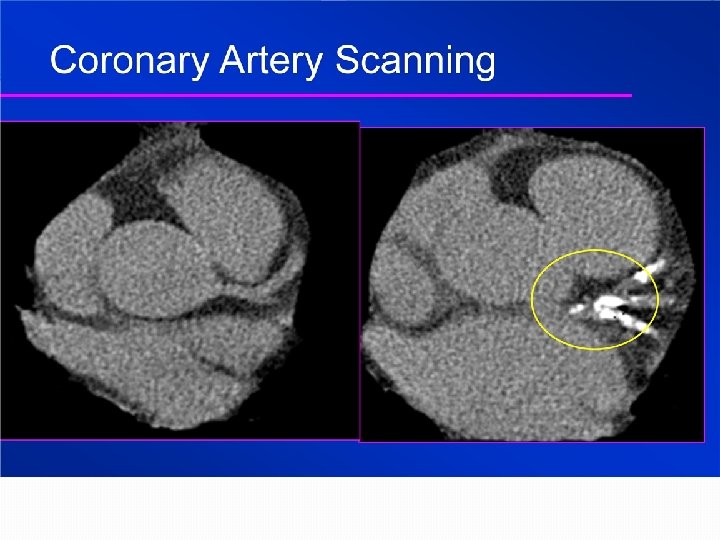

Cardiac CT Fast Scan Times Minimal Radiation Instant Results

WHAT DOES CORONARY ARTERY CALCIFICATION MEAN? Atherosclerosis present in this vessel Higher levels of coronary calcium correlate with higher risks Zero calcification (none seen) suggests a very low probability of obstructive disease and less than 1% chance of heart attack and stroke over the next 5 years

Who Should Have this Test? Low risk men over 45 Higher risk men over 35 with one or more of the following: Diabetes High Blood Pressure Smoking High Cholesterol Family History of Heart Disease